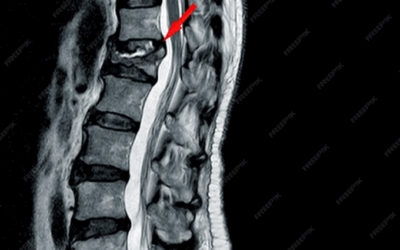

Omurilik Tümörü

Omurilik Tümörü Nedir? Omurilik tümörü, omuriliğin içinde, omuriliği çevreleyen zarın içinde veya omurga kemiklerinin içinde büyüyen anormal hücre çoğalmalarıdır. Bu tümörler, iyi huylu (benign) veya kötü huylu (malign)...